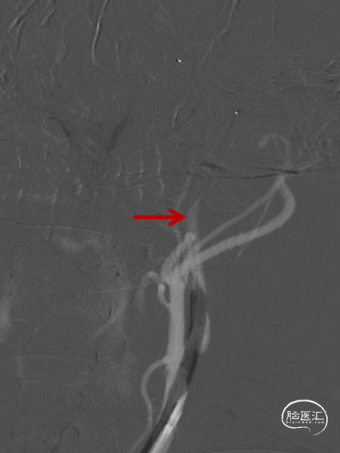

术前造影提示左侧颈内动脉自起始部闭塞,前交通动脉开放,同侧大脑前动脉及大脑后动脉皮层对左侧半球形成皮层侧支代偿。

微导管微导丝配合下多次尝试通过颈内动脉起始部闭塞段未能成功,在125mm多功能导管配合下,将微导管及Command微导丝成功越过颈内动脉起始部闭塞段,微导管造影确认在颈内动脉真腔,但远端未见显影,考虑血栓所致。静脉推注替罗非班8ml,并以6ml/h持续泵入。